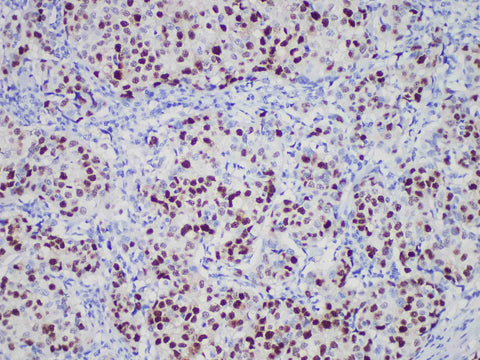

PR Monoclonal Antibody Stored at 2~8°C

Applications IHC-P

Cellular Localization nucleus

Tissue Specificity Breast cancer

Progesterone receptor (PR) has two isomers, pra (94kda) and pRb (114kda), whose function is that transcription factors exist in normal endometrial and mammary epithelial cells after ligand activation. Recently, a large number of studies on breast cancer have shown that most of the ER and PR positive data are effective in endocrine therapy, with high remission rate, low recurrence rate and good prognosis. Even if there is only one positive patient in ER or PR, its prognosis is better than the two all negative patients, so PR has become one of the routine examination items for breast cancer patients.